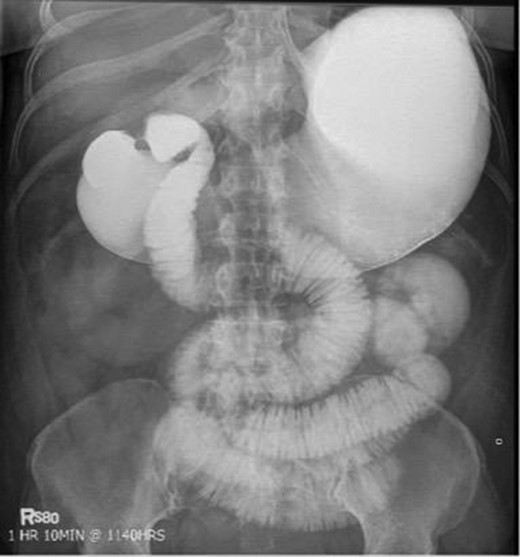

Laboratory studies were remarkable for leukocytosis, and an elevated lactate that improved with hydration (Fig. 1), while urinalysis was unremarkable. Abdominal CT scan obtained at this time demonstrated a partial SBO in the mid-small bowel as well as inflammation and thickening of the duodenum. A small bowel series was ordered, and showed high grade SBO (Figs 2–5).

Fluoroscopic barium study demonstrating oral contrast agent progression through the small bowel at 30 min after ingestion.